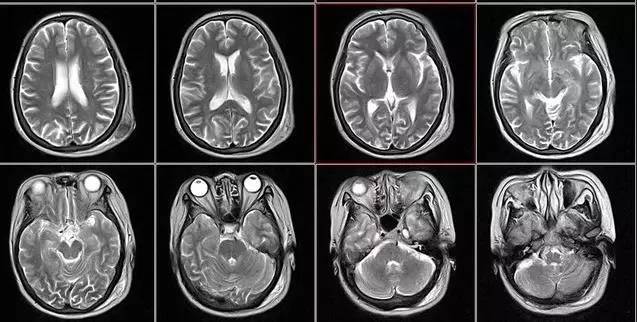

核磁共振:搖一搖再看

核磁共振機使用較強大的磁場,使人體中所有水分子磁場的磁力線方向一致,這時磁共振機的磁場突然消失,身體中水分子的磁力線方向,突然恢復(fù)到原來隨意排列的狀態(tài)。簡單說就相當(dāng)于用手搖一搖,讓水分子振動起來,再平靜下來,感受一下里面的振動。所以,核磁共振(MRI)也被戲說為是搖搖看的檢查。